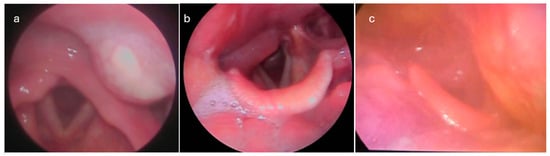

Although clinical findings are of the greatest importance in the suspicion of a PMA, a CT scan with contrast is the “gold standard” to set the diagnosis [7] (Figure 3 and Figure 5). Abscess protrusion into the pharyngeal lumen may give the false impression of a parapharyngeal abscess; however, the PMS is located in the lateral pharyngeal wall, between the pharyngeal mucosa and the pharyngeal constrictors, extending under the hyoid bone and passing medially to it. On the contrary, other spaces extend laterally to the hyoid bone (e.g., carotid space), whereas, for others (e.g., parapharyngeal space), it represents their lower border. Ultrasonography cannot identify the PMS adequately, while MRI may also be of use in selected cases [7]. The high diagnostic accuracy of MRI can be utilized in order to specify the anatomic relation of the abscess with the pharyngeal constrictors, differentiating between PMAs and deeper-extending abscesses [11]. However, the practical need for imaging and the cost-effectiveness can be controversial, as a significant number of cases can resolve rapidly. Nevertheless, unless strongly contraindicated, imaging is highly recommended, so that deeper counterpart involvement may be excluded, especially in cases with severe symptoms and clinical findings.

Figure 5. CT images of different categories of DNIs: (a) left-side PMA protruding into the pharyngeal lumen, passing medially to the hyoid bone; (b) right-side peritonsillar abscess, extending to the parapharyngeal space towards the right carotid artery and jugular vein; and (c) extended right-side parapharyngeal and retropharyngeal abscess. Arrows and stars indicate the margins of the abscess.